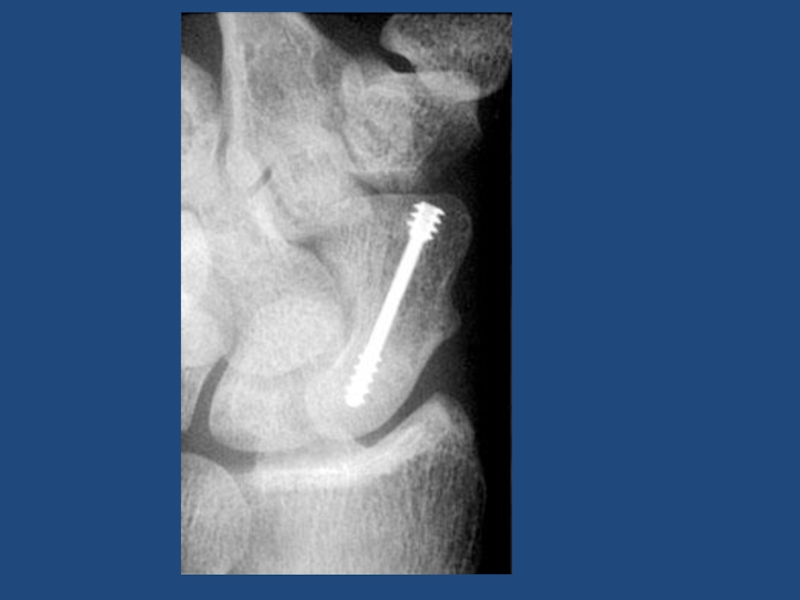

Внутрисуставной ???

Перелом таранной кости